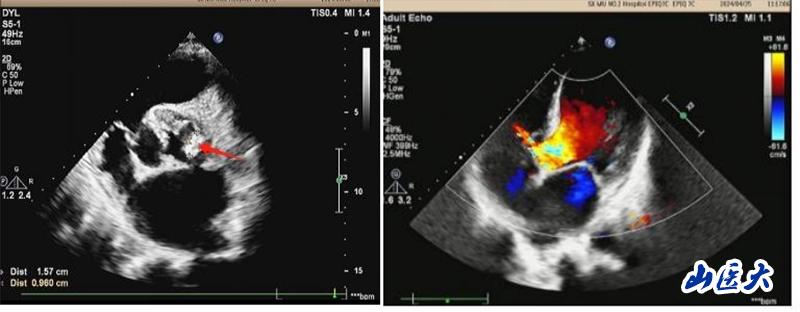

患者系一名中年男性,20余年前在当地医院体检发现心脏杂音,但未进一步诊治。2024年3月初开始间断出现发热、胸闷、气短,体温高达38.5℃,伴咳嗽、咳白色痰液,不能平卧休息,伴双下肢水肿、食欲不振,就诊于我校第二医院心血管内科。行心脏彩超等辅助检查后诊断为:感染型心内膜炎、主动脉瓣赘生物,主动脉瓣二瓣化畸形伴重度关闭不全,二尖瓣中度关闭不全,室间隔缺损,肺动脉高压。布氏杆菌感染进一步加重了心功能衰竭。心血管内科周荣副主任医师为其制定了精细的治疗方案,给予抗感染、利尿等多种措施治疗后,患者上述症状稍缓解,但须手术治疗方能彻底痊愈。

患者转入心胸外科后,马捷主任医师根据患者病史长、心功能差、合并多个瓣膜病变和长期心内分流畸形的病情特点,为其制定了个体化的诊疗方案,积极调整患者心、肺功能,改善营养状态,创造手术机会。5月14日,马捷主任医师、李强副教授团队在麻醉科、手术室等多学科的密切配合下,为患者成功实施了心脏手术:切除病变的主动脉瓣、植入主动脉机械瓣、行室间隔缺损修补术以及二尖瓣成形术。经过医护团队的不懈努力,以及患者和家属的积极配合,患者经受住了复杂心脏手术的风险,终获新生,体力、睡眠和食欲都恢复到正常人的水平,心脏恶液质得以逆转,目前即将痊愈出院。术后复查心脏超声,各瓣膜功能恢复良好。